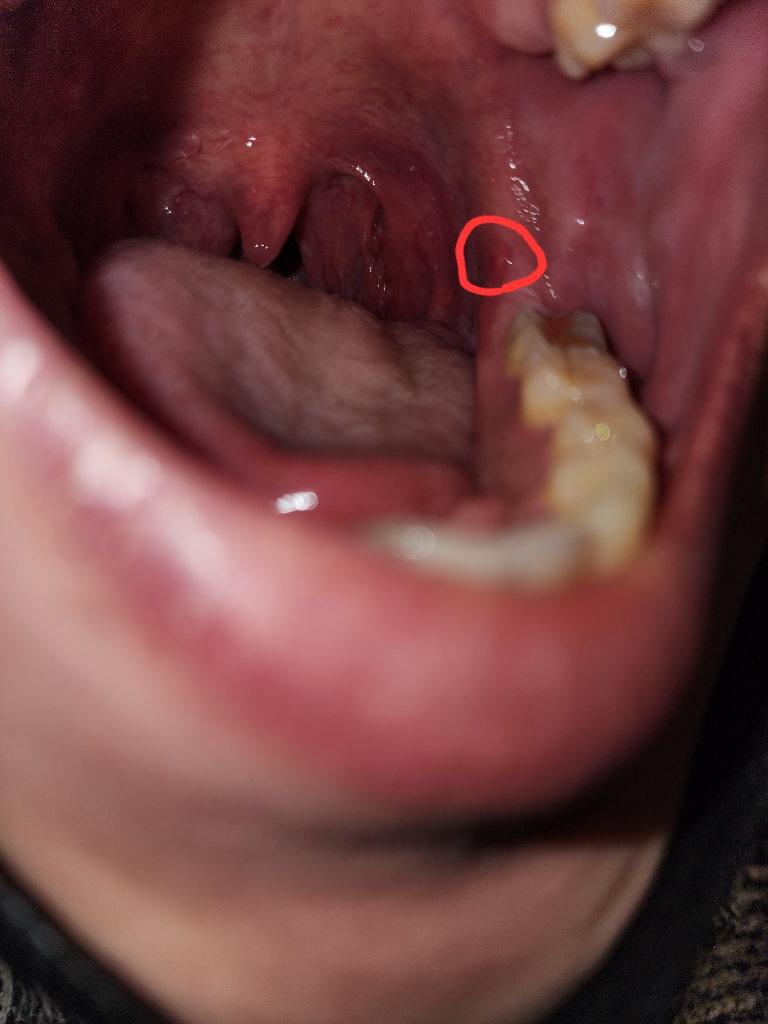

입안 어금니쪽 잇몸에 투명물집같은게 생겼는데 왜이런거죠?

밥먹다가 어금니 뒤쪽 잇몸에 이물감이 느껴져서 만저보니 조그마한 투명물집 같은게 있네요

아프진않고 아린느낌 거슬리는느낌? 입니다

• 1번 째 사진